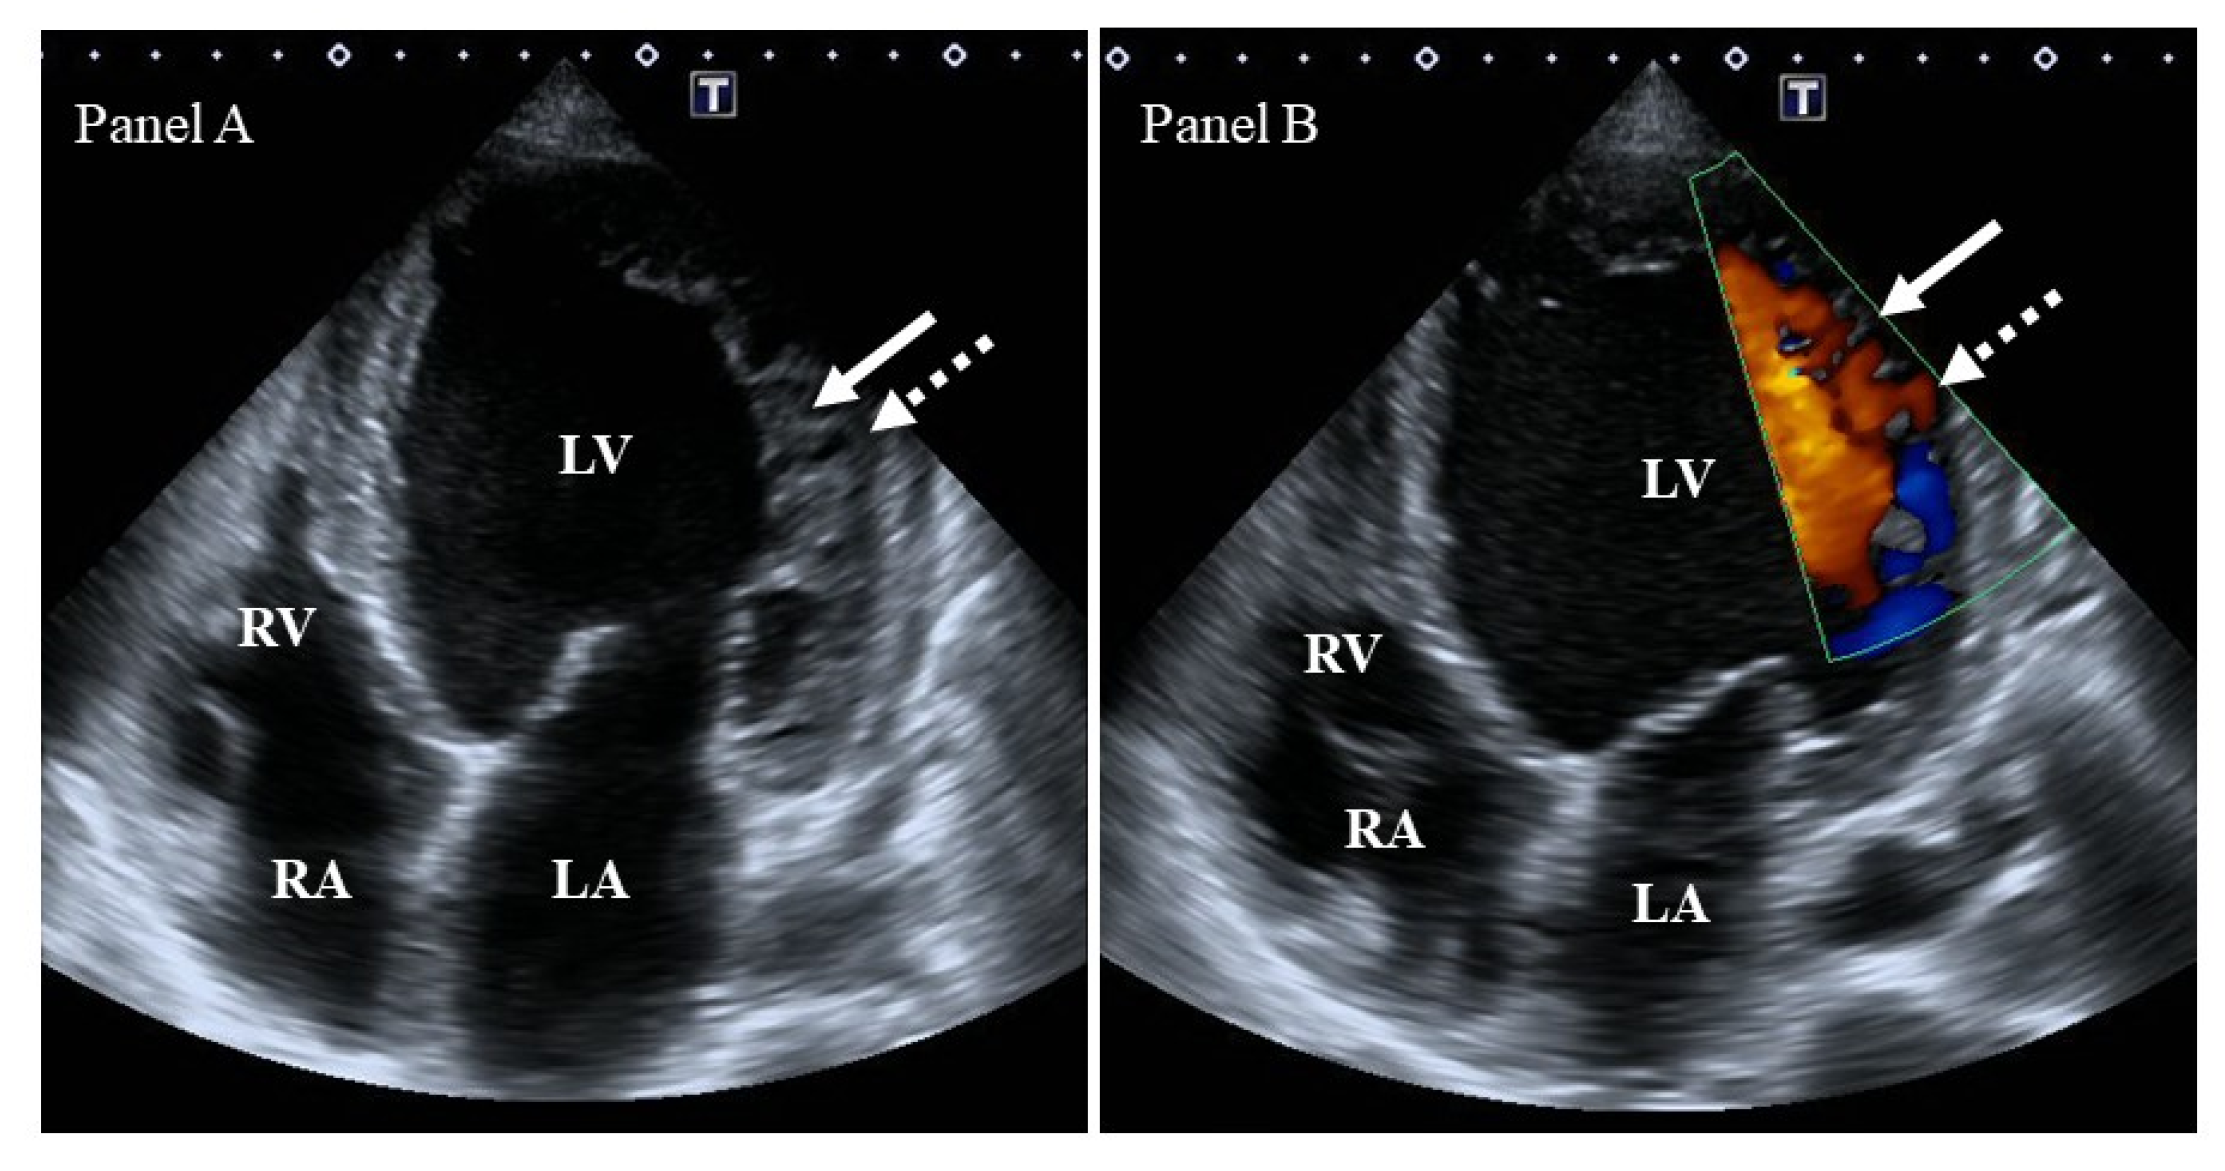

- Jenni’s criterion is more complicated and takes into account a number of other factors: (I) the presence of a two-layer myocardial structure with a thin compacted and a thicker noncompacted myocardium, (II) the ratio of noncompacted to compacted myocardium > 2 at the end-systole, (III) the absence of coexisting cardiac structural abnormalities, and (IV) excessive prominent trabeculations and deep intertrabecular recesses filled with intraventricular blood with color Doppler imaging. Parameters are measured in parasternal short-axis views [4].

| Mitral valve | MA was dilated and functionally impaired. | [87] | 20 |